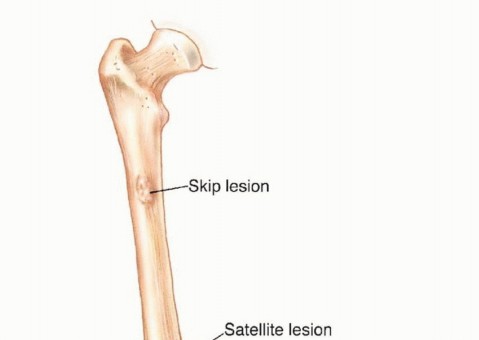

This pseudocapsule consists of compressed tumor cells, a fibrovascular zone of reactive tissue, and a variable inflammatory component that interacts with the surrounding normal tissues. Crucially, the pseudocapsule is not a true anatomic barrier. Microscopic tumor extensions, known as satellite lesions, frequently penetrate this reactive zone and reside in the immediately adjacent normal-appearing tissue. Therefore, a biopsy that breaches the pseudocapsule inevitably contaminates the surrounding tissue planes with malignant cells.

Compartmental Anatomy and Skip Metastases

The concept of compartmental anatomy is paramount in orthopedic oncology. A compartment is defined as an anatomic space bounded by natural barriers to tumor extension, such as major fascial septa, cortical bone, articular cartilage, and dense tendinous insertions. Tumors confined entirely within a single compartment (intracompartmental, Enneking Stage T1) have a significantly better prognosis and require less morbid resections than those extending beyond these boundaries into adjacent spaces (extracompartmental, Enneking Stage T2).

Furthermore, aggressive high-grade sarcomas may shed cells that break through the pseudocapsule and travel along longitudinal tissue planes to form metastases within the same anatomic compartment, entirely separate from the primary mass. These are termed "skip metastases." By definition, these are locoregional micrometastases that have not passed through the systemic circulation.